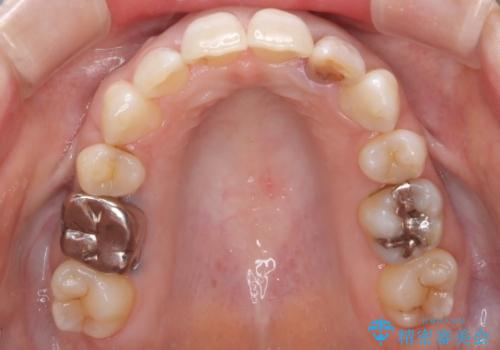

重度のガタガタと出っ歯をワイヤーによる抜歯矯正で整った歯並びへ

- 全体的ながたがたを主訴に来院されました。

上顎の前歯は前方に傾斜して、下顎の前歯は強いガタガタが見られました。

前から4番目の歯を上下左右合計2本抜歯して、歯並びを整える計画としました。

ワイヤー矯正にて治療しました。